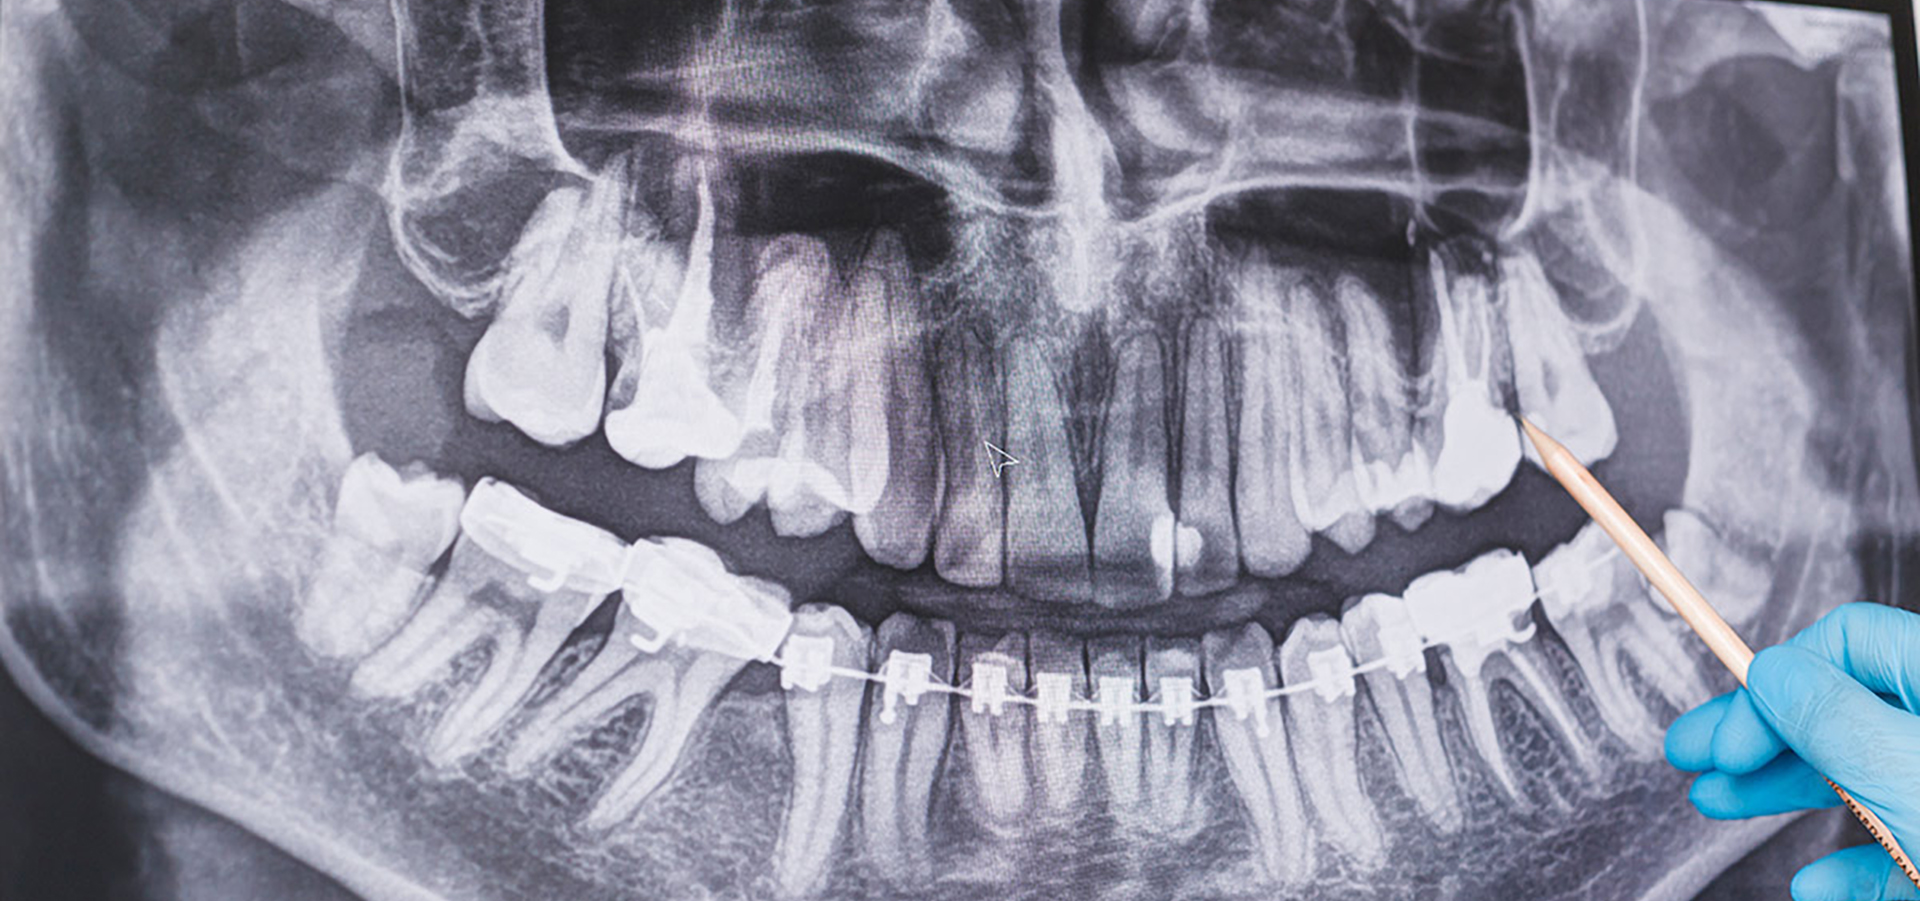

矯正專科

牙齒矯正的原理,是利用牙齒矯正器的微型機器力,移動牙齒達到牙齒矯正的目的,由於人體骨骼是活性的器官,透過外力可以緩慢移動牙齒與口腔肌肉,讓原本錯亂的牙齒,逐漸到達理想的位置。